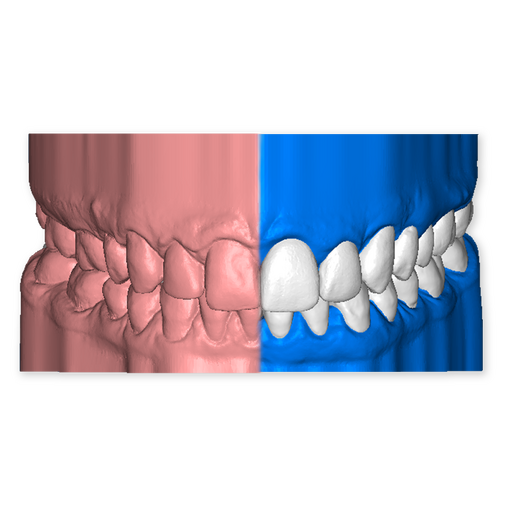

The DSD Interdisciplinary is a digital wax up of the upper and lower arches, designed considering a facially-driven, clinical and functional analysis of the patient.

It is our most comprehensive planning option, and includes all the 3D treatment simulations needed for each case, such as ortho, perio, implants, grafts and orthognathic surgery.

Our 3D simulations showcase various treatment suggestions, facilitating a deeper understanding of the required procedures. This leads to the creation of a broader treatment plan and enables a more efficient communication with your patients.